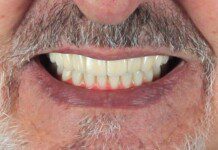

The definitive zirconia bridge is screwed in place and the screws are tightened. The final restoration is strong and able to restore both esthetics and function.

The definitive zirconia bridge is screwed in place and the screws are tightened. The final restoration is strong and able to restore both esthetics and function.

The definitive zirconia bridge is screwed in place and the screws are tightened. The final restoration is strong and able to restore both esthetics and function.

The definitive zirconia bridge is screwed in place and the screws are tightened. The final restoration is strong and able to restore both esthetics and function.